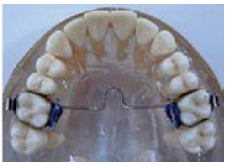

Figure 13. Bite plate.

Figure 13